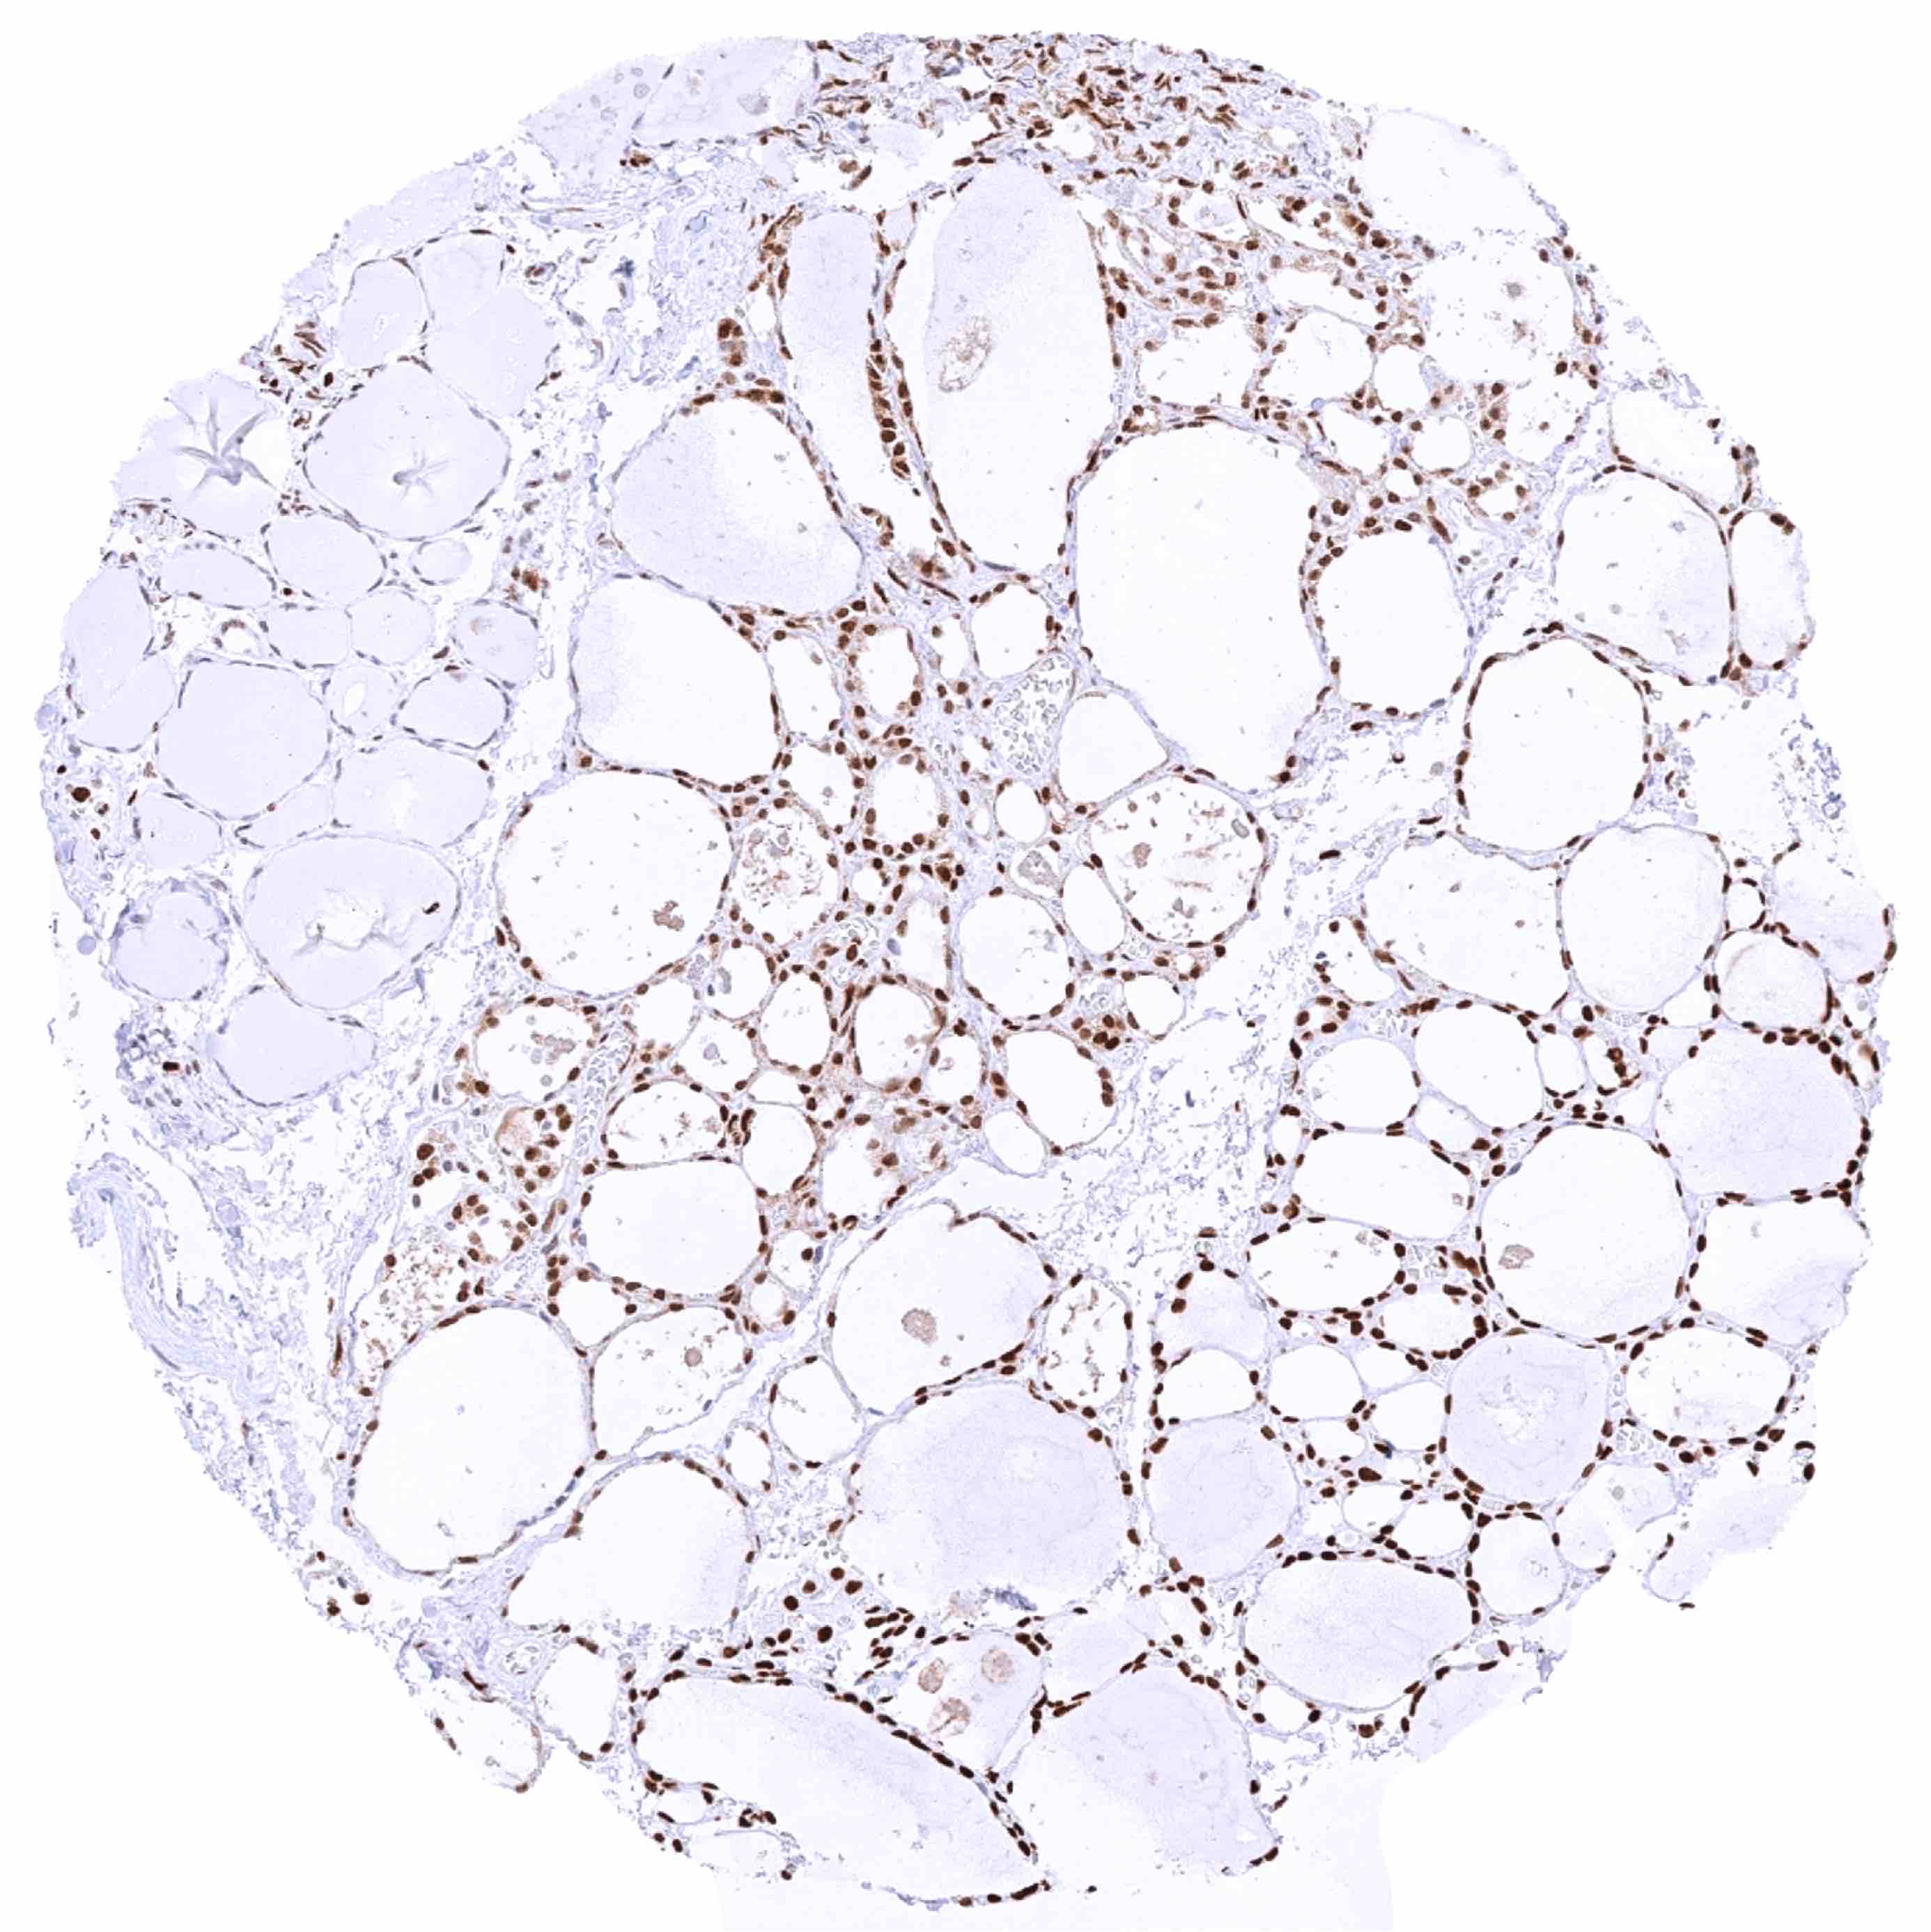

Thyroid gland